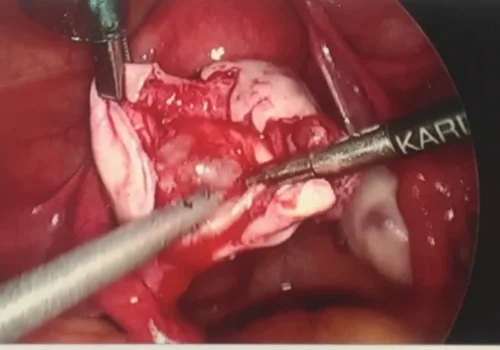

Procedure

She subsequently underwent laparoscopic left ovarian dermoid cystectomy. The pathology revealed a benign dermoid cyst with a molar tooth. This large area of sharp calcification is likely to have caused the pain.